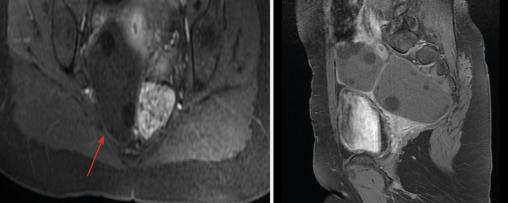

Une patiente âgée de 44 ans, opérée pour un kyste hydatique hépatique seize ans auparavant, consulte pour des douleurs abdomino-pelviennes intermittentes et une irrégularité du cycle menstruel. L‘examen clinique révèle une masse annexielle droite, sensible et indépendante de l’utérus ainsi qu’une hépatosplénomégalie. L’état général est conservé. L’hémogramme montre une hyperleucocytose à 24 800/mm3 à prédominance de neutrophiles et une anémie hypochrome microcytaire. La sérologie hydatique est positive. L’échographie pelvienne met en évidence deux formations en régions ovarienne et rétro-utérine droites, bien limitées, renfermant plusieurs structures serpigineuses rappelant des membranes proligères, et des images multi­vésiculaires, mesurant 42 × 40 mm et 80 × 73 mm. Ces observations permettent d’évoquer le diagnostic de kyste hydatique ovarien organique classé type III de la classification de Gharbi. Le balayage hépatosplénique trouve des kystes hydatiques spléniques et hépatiques du segment IV classés type III de la classification de Gharbi. La tomodensitométrie (TDM) abdomino-pelvienne (fig. 1) confirme la présence de deux formations ovariennes et rétro-utérines droites ovalaires, mal limitées, à paroi fine, de densité liquidienne, qui renferment une membrane décollée avec une localisation hépatosplénique. L’imagerie par résonance magnétique (IRM) pelvienne (fig. 2 et 3) précise l’aspect des deux volumineuses masses : une latéro-utérine et l’autre rétro-utérine à droite, de contours réguliers, bien limitées, à paroi fine, de signal hétérogène T2, renfermant des vésicules filles en hypersignal T2 franc liquidien sans restriction de la diffusion et ne se rehaussant pas après injection. La patiente a bénéficié d’une intervention chirurgicale, qui a trouvé deux kystes pelviens latéro-utérins de 8 cm de diamètre pour le plus volumineux. L’étude anatomopathologique a confirmé le diagnostic de kyste hydatique.  Les suites postopératoires ont été simples, avec un traitement médical adjuvant par albendazole.